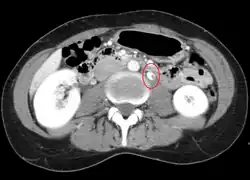

CT and MRI with contrast can be used afterward to confirm compression by the AA and SMA with comprehensive measurements of the abdominal vasculature. A "beak sign" can often be seen in CT scans due to the LRV compression. However, CT and MRI cannot demonstrate the flow within the compressed vein. These two modalities can be used to confirm other evidence for NCS such as back-up of blood flow into the ovarian veins.[11][6]